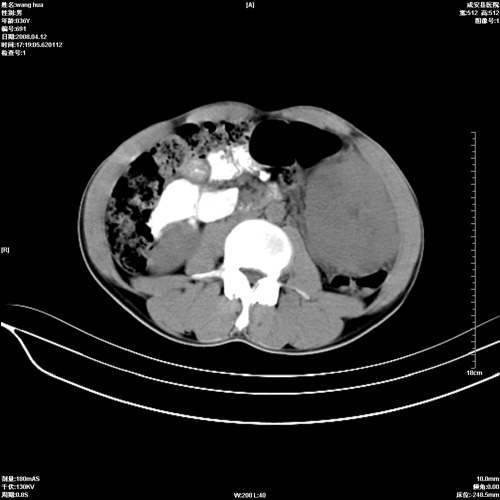

标题: CT12809:男36岁,自感上腹胀5天,B超诊断为脾肾之间占位,血 [打印本页]

标题: CT12809:男36岁,自感上腹胀5天,B超诊断为脾肾之间占位,血

请各位老师先分析一下定位 明天做增强

脾脏明显增大,其内见巨大低密度灶,境界不清,病史较短,考虑恶性病变脾血管内皮细胞肉瘤可能。建议增强扫描与脾脏淋巴瘤及血管瘤鉴别。